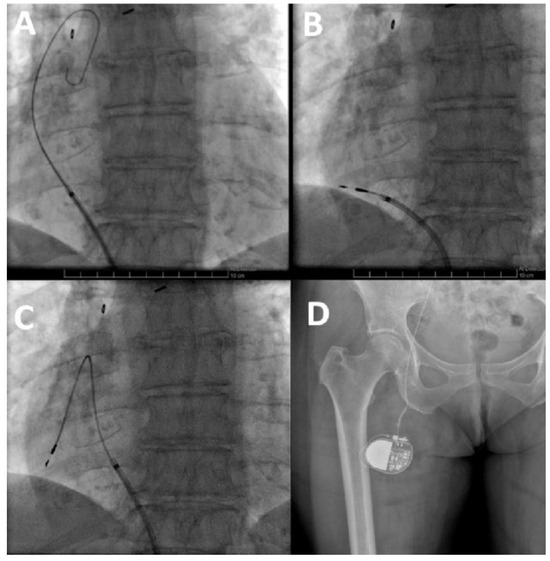

Standard Pacemaker Implantation via Femoral Venous Access

Pacemaker implantation via the femoral vein has been described since the 1980s. This technique is not very well known, but may be useful in some circumstances. We describe a case of a patient with sinus dysfunction without superior venous access, in...